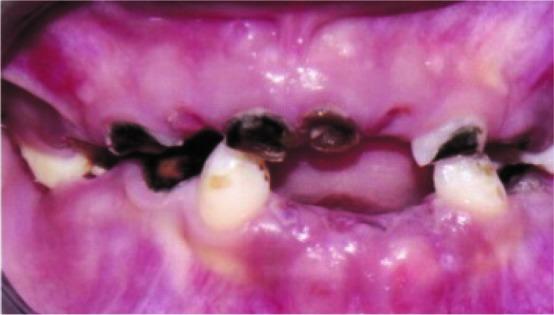

Goldenhar syndrome (GHS) is a complex syndrome characterized by relation of mandibular hypoplasia, abnormality of the ear, ocular dermoid and vertebral disorders and hemi facial macrosomia. Treatment protocol depends on the patient's age and systemic clinical presentations, with a multidisciplinary method often being required. This case report describes a typical 6-year-old female patient who presented to the Department of Pediatric Dentistry, Faculty of Dentistry, University of Medical Sciences, Kerman, Iran with mandibular hypoplasia, facial asymmetry, ear tags and ocular dermoid after plastic surgery. Diagnosis was based on clinical aspects, radiology and laboratory findings. GHS is a developmental complaint that can disturb many aspects of the patient's life; therefore, immediate treatment from birth is necessary.

戈尔登哈综合征(GHS)是一种复杂的综合征,其特征为下颌发育不全、耳部异常、眼皮样囊肿、脊柱疾病以及半侧颜面巨大症。治疗方案取决于患者的年龄和全身临床表现,通常需要多学科方法。本病例报告描述了一名典型的6岁女性患者,她因下颌发育不全、面部不对称、耳赘和眼皮样囊肿在接受整形手术后就诊于伊朗克尔曼医科大学牙科学院儿童牙科。诊断基于临床症状、放射学和实验室检查结果。戈尔登哈综合征是一种发育性疾病,会干扰患者生活的许多方面;因此,从出生起就需要立即进行治疗。